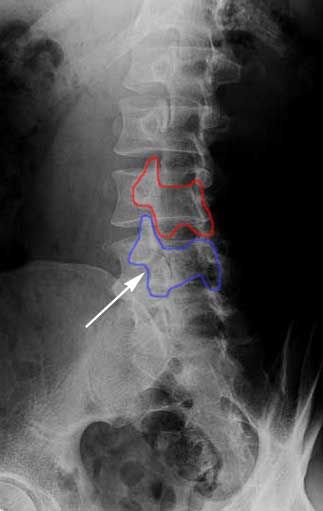

X-RAY SHOWING A PARS FRACTURE DEFECT

THE WHITE OUTLINE SHOWS THE SLIPPAGE.

When we look at the spine from the side, we can imagine a scotty dog. It is outlined above. The pars fracture is seen as a collar around the dog's neck. Instability and movement can cause the neck to widen. We will see this below in an X-ray example.